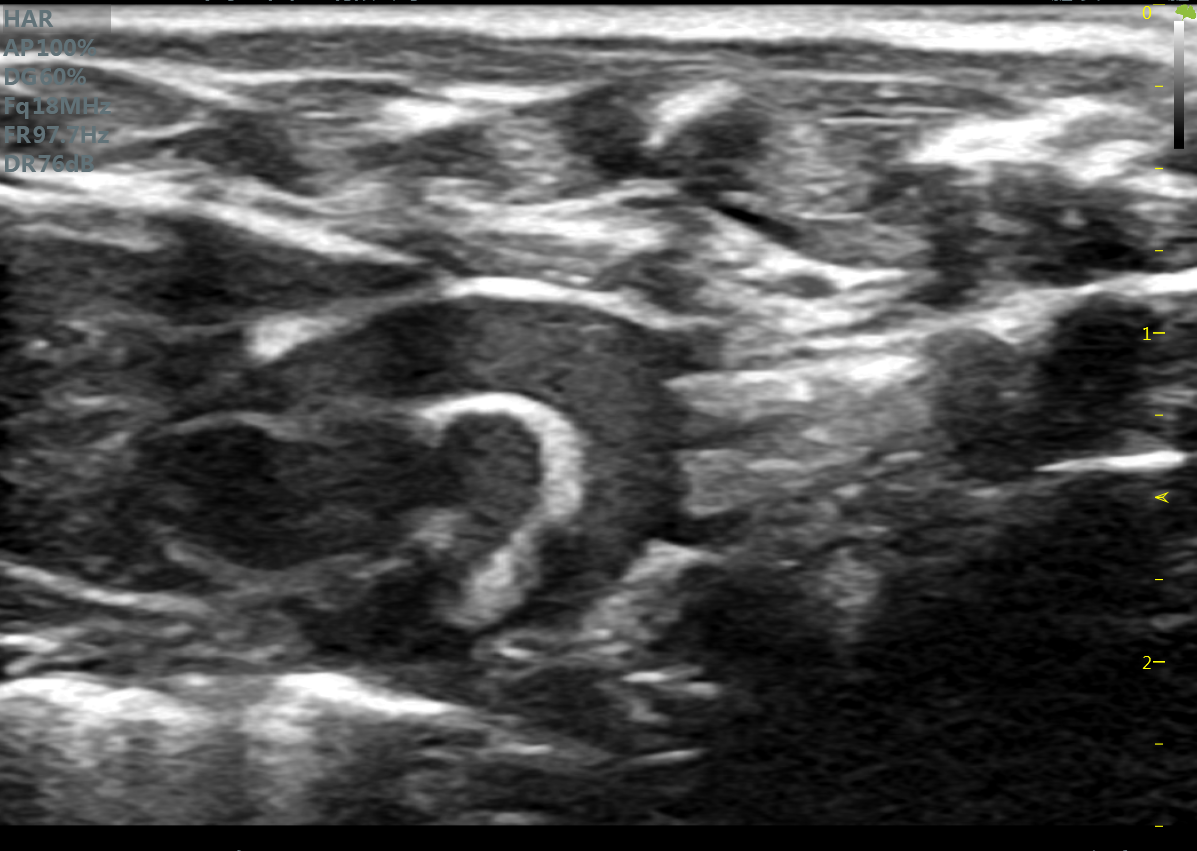

大鼠长轴B型 大鼠主动脉弓